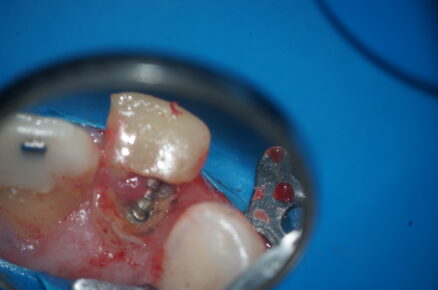

Figura 1: Aspecto clínico inicial

Figura 2: Aspecto do preparo cavitário e isolamento do campo operatório